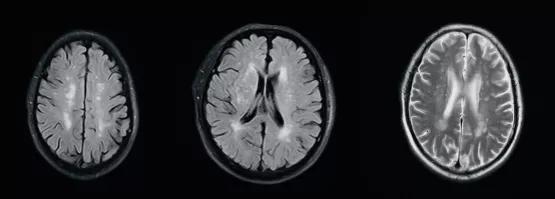

(FLAIR序列及T2WI序列显示缺血性脱髓鞘病变)

(常见无症状炎性脱髓鞘病变)